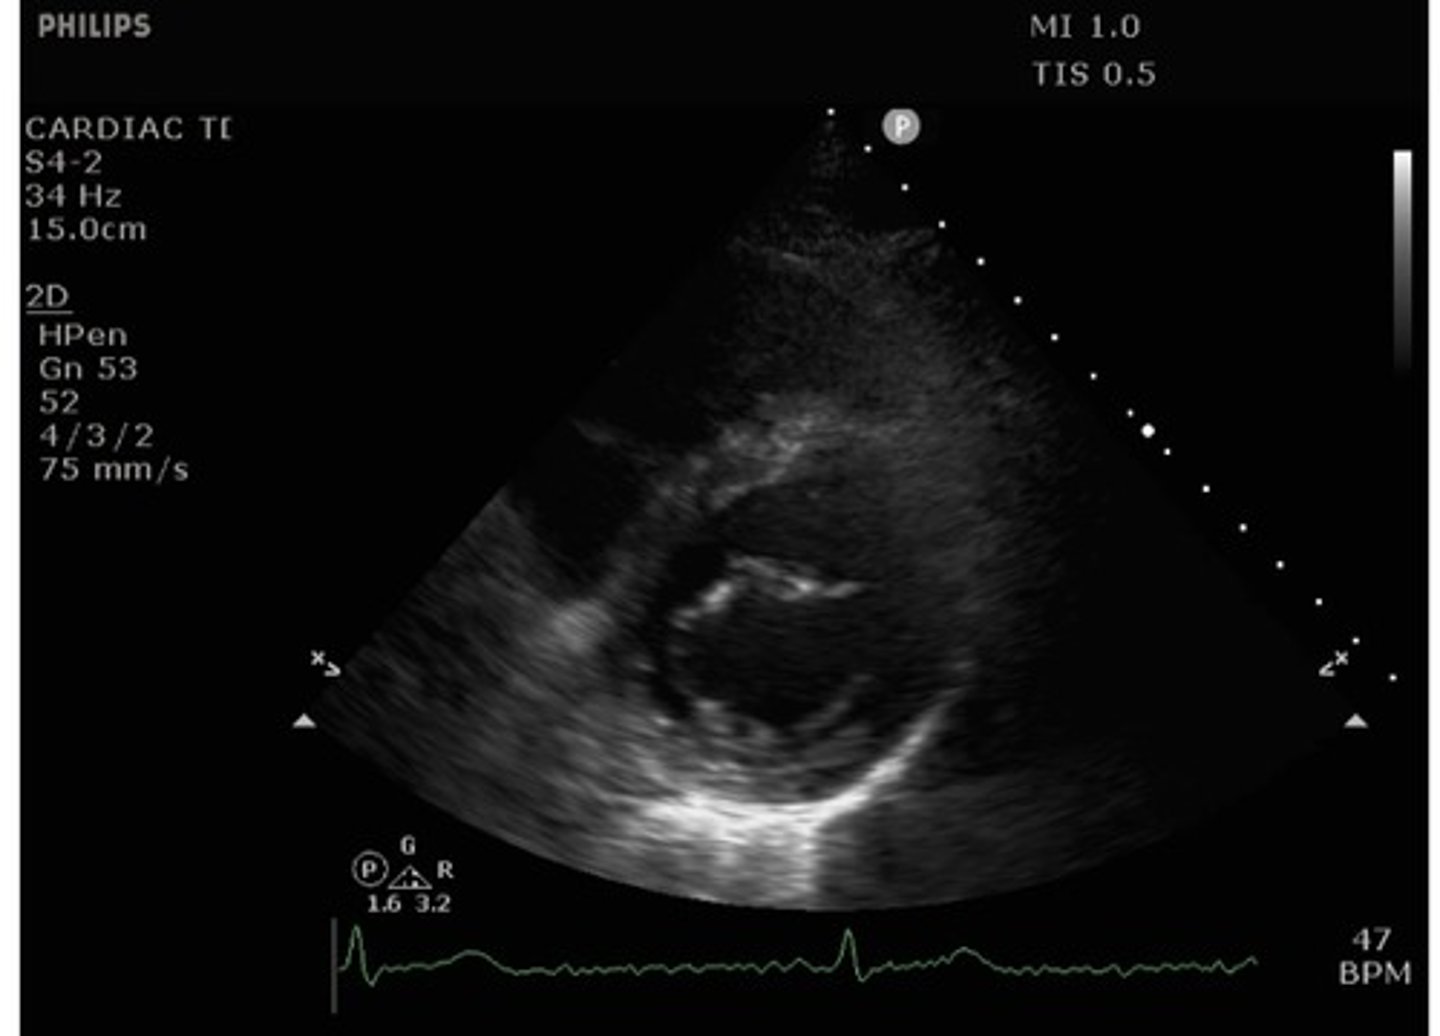

parasternal short axis mitral valve view

what view is this?

what structures are seen with parasternal short axis mitral valve view?